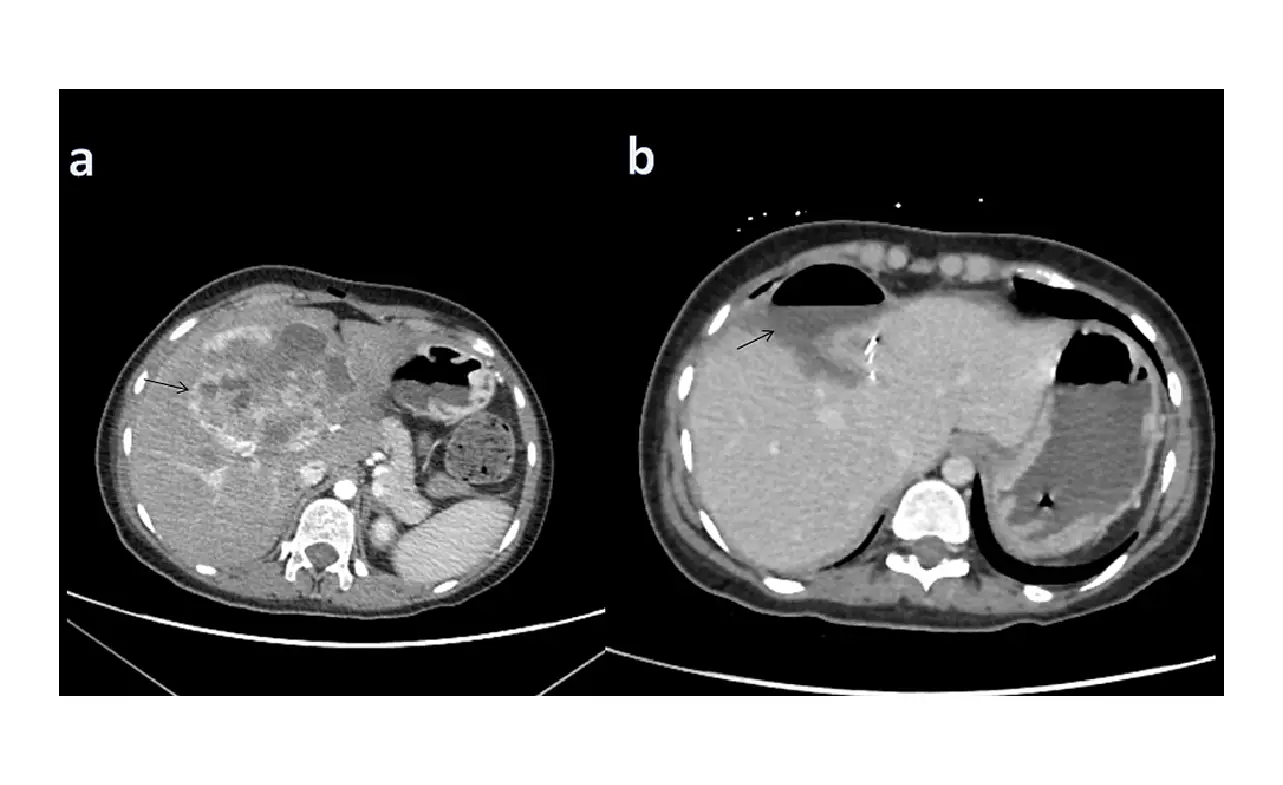

• CT Scan: Provides detailed images of the liver and surrounding organs.